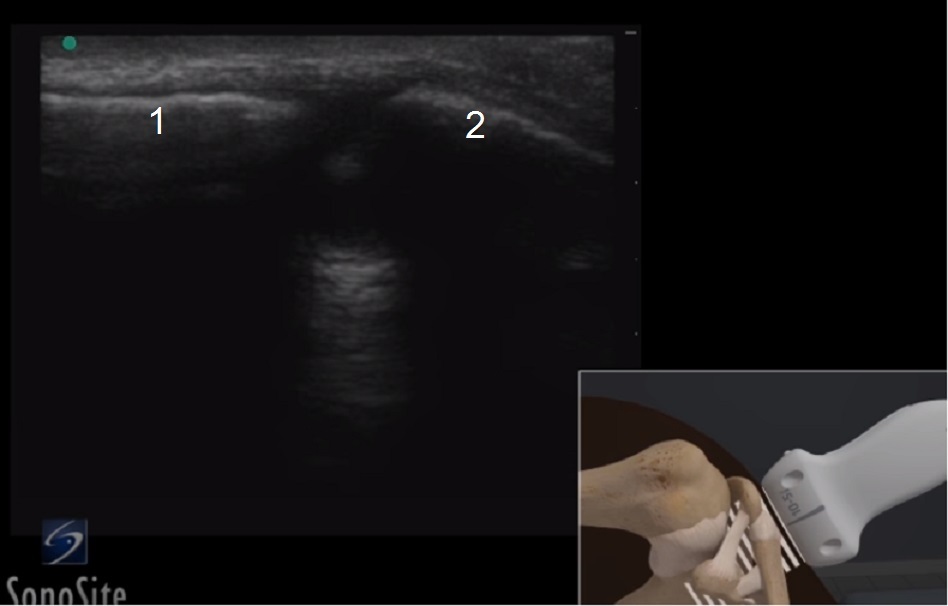

肩鎖関節の解剖学 1 画像

肩峰

鎖骨遠位端